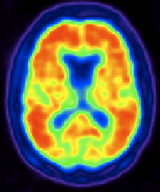

Los escaneos TEP también usan radiofármacos para crear imágenes tridimensionales. La principal diferencia entre los escaneos TCEFU y TEP es el tipo de radiotrazadores utilizados. Mientras que los escaneos TCEFU miden los rayos gamma, la descomposición de los radiotrazadores usados con escaneos TEP produce pequeñas partículas llamadas positrones. Un positrón es una partícula con aproximadamente la misma masa que un electrón, pero con carga opuesta. Estas reaccionan con los electrones en el cuerpo y cuando estas dos partículas se combinan se aniquilan entre sí. Esta aniquilación produce una pequeña cantidad de energía en la forma de dos fotones que se disparan en direcciones opuestas. Los detectores del escáner TEP miden estos fotones y usan esta información para crear imágenes de los órganos internos.

El propósito principal de los escaneos TEP es detectar el cáncer y monitorear su evolución, la respuesta al tratamiento y para detectar metástasis. La utilización de glucosa depende de la intensidad de la actividad celular y de los tejidos, por lo que se incrementa enormemente en las células cancerosas que se dividen rápidamente. De hecho, el grado de agresividad de la mayoría de los cánceres es más o menos paralelo a su grado de utilización de glucosa. En los últimos 15 años, las moléculas de glucosa radiomarcadas ligeramente modificadas (fluorodesoxiglucosa F-18 o FDG) han demostrado que son el mejor trazador para detectar el cáncer y su diseminación metastática en el cuerpo.

Recientemente, una sonda TEP fue aprobada por la FDA para ayudar en el diagnóstico preciso de la enfermedad de Alzheimer, la cual anteriormente se podía diagnosticar con precisión solamente después del fallecimiento del paciente. En ausencia de esta prueba de imágenes TEP, la enfermedad de Alzheimer puede ser difícil de diferenciar de la demencia vascular u otras formas de demencia que afectan a las personas mayores.